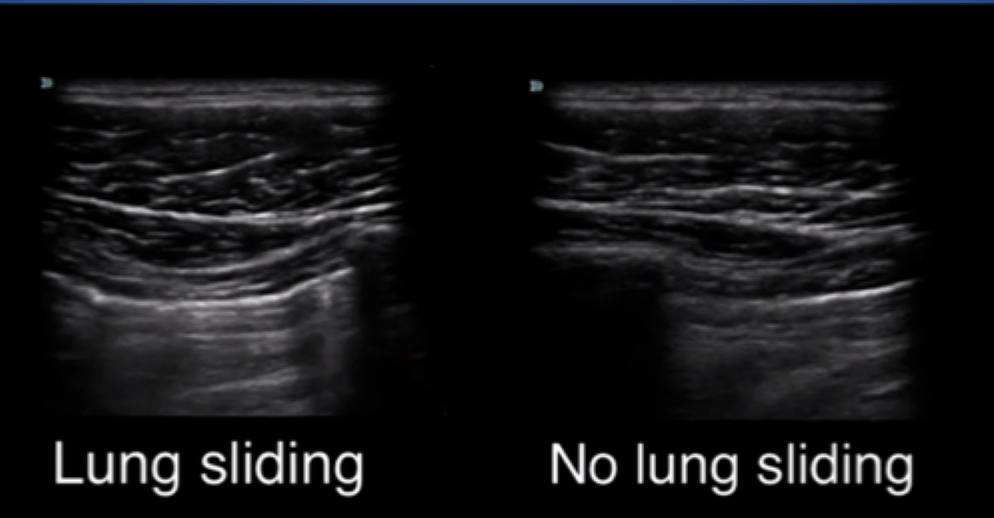

pneumothorax

DX = visceral pleural lines

what sign is this in pneumothorax

deep sulcus sign in supine pts